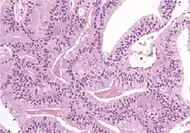

Non acinar (or mixed acinar/ non-acinar) adenocarcinoma | Ductal adenocarcinoma | 3% to 12.7%[8][notes 1] | ![]() |

||||

Ductal adenocarcinoma may have a prominent cribriforming architecture, with glands appearing relatively round, and may thereby mimic intraductal adenocarcinoma, but can be distinguished by the following features:[10]

Feature | Ductal adenocarcinoma | Intraductal adenocarcinoma |

True fibrovascular cores in micropapillary architecture | Present | Usually absent |

Cribriform lumens | Lined by pseudostratified, columnar cells | Punched out lumens lined by cuboidal cells |

Basal cell markers | Usually negative | Usually positive |